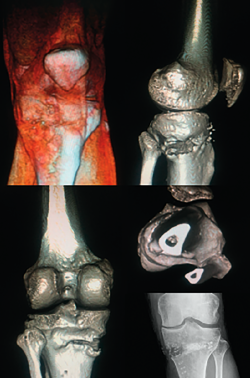

We should bear in mind that although the indication of osteotomy resides in varus correction (coronal plane), the osteotomy will also affect the sagittal and axial planes (Figure 5).

Figure 5. Control computed axial tomography view of an opening valgus-producing tibial osteotomy.